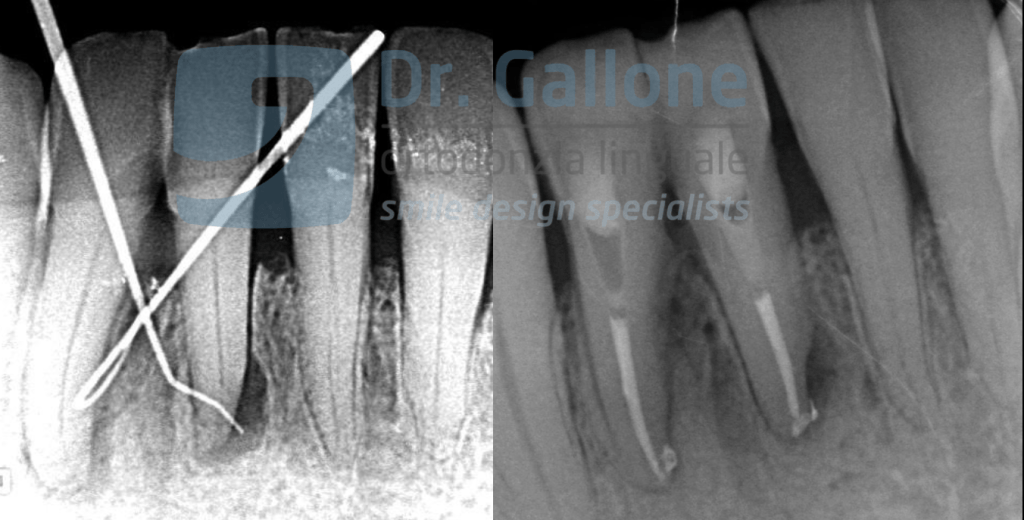

Devitalization of lower central incisors with lesion, control at 3 months. Case of Dr. Caschetto